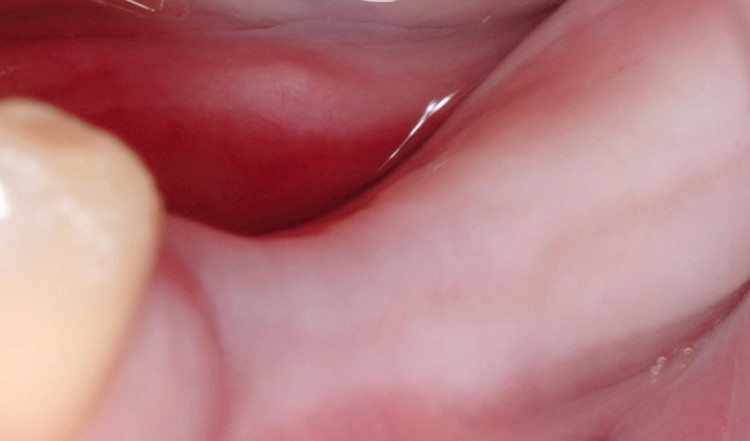

真实病例